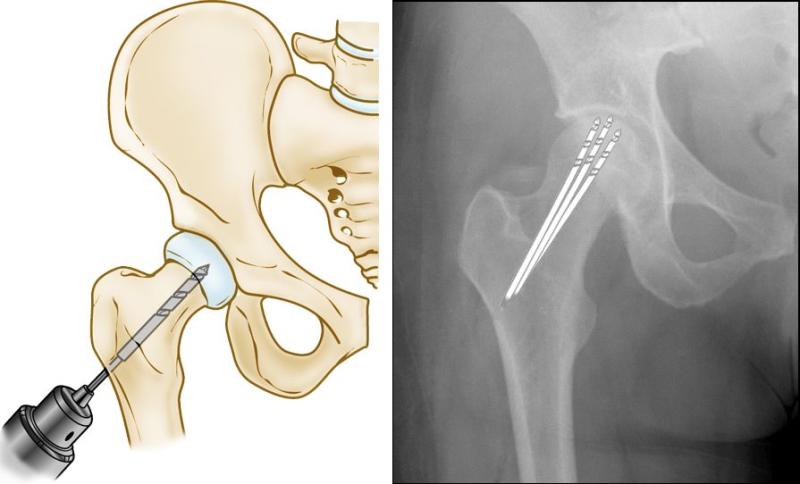

Osteonecrosis treatment refers to therapeutic interventions aimed at managing and treating osteonecrosis, a condition characterized by the death of bone tissue due to reduced blood flow. This condition, also known as avascular necrosis, primarily affects joints such as the hip, knee, shoulder, and ankle, leading to pain, joint stiffness, and potential collapse of the affected bone. Treatment options depend on the stage and severity of osteonecrosis and may include conservative measures such as pain management with nonsteroidal anti-inflammatory drugs (NSAIDs) or analgesics, limiting weight-bearing activities, and physical therapy to maintain joint mobility and strength. For more advanced cases, surgical interventions like core decompression (removal of necrotic bone), bone grafting, osteotomy (repositioning of bones), or joint replacement surgery may be necessary to relieve pain, improve joint function, and prevent further deterioration of the affected bone. Treatment plans are tailored based on individual patient factors, including age, overall health, and the extent of bone damage.